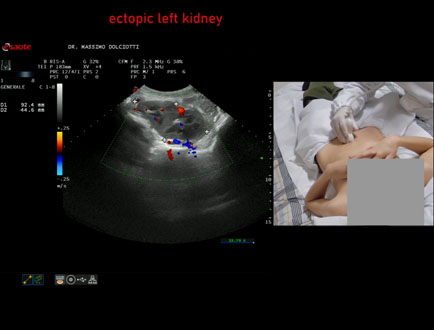

Data inserimento: 31/03/2026

Ecografia del: 16/03/2026

Strumento: Esaote MyLab Eight

Sonda: Convex Multifrequenza 1-8 MHz

Età Paziente: M 12 anni

Motivazione dell'esame: riscontro occasionale di ectopia renale sinistra

Commento all'esame: le immagini ed il video documentano il rene sinistro ectopico in sede pelvica, di ecostruttura regolare e morfovolumetria normale, con diametro bipolare di 99 mm (v.n. 90-120 mm) x 37 mm, non dilatazione della via escretrice sinistra.

Conclusioni: rene sinistro ectopico (ectopic left kidney).